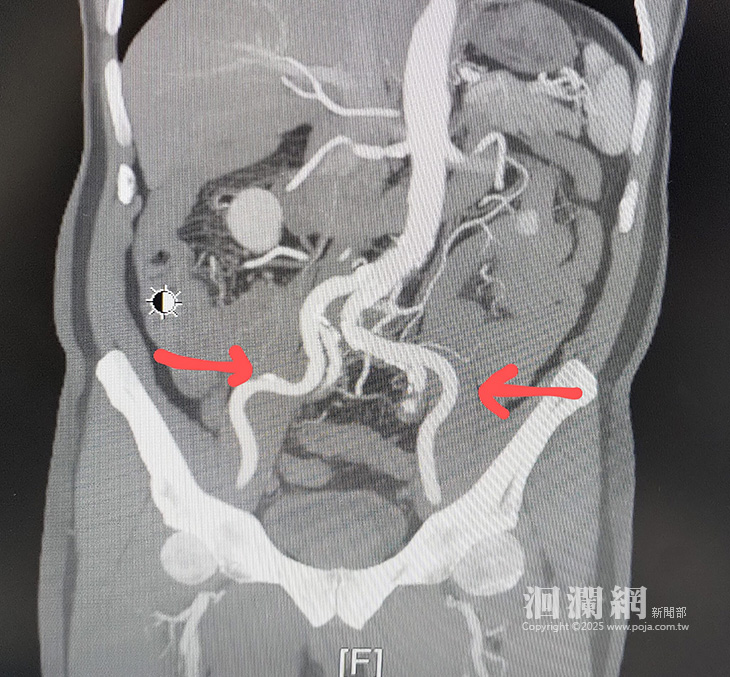

【飯後腹脹竟是致命警訊!門諾心血管團隊鬼門關搶人】

花蓮1名75歲吳先生苦於飯後腹脹難忍,原以為是胃食道逆流搞怪,但吃藥2周未見效,照胃鏡也沒找到病因,卻意外發現主動脈弓潰瘍、冠狀動脈狹窄、堵塞;吳翁住院期間還突發心肌梗塞,一度情況危急。門諾醫院心臟血管外科主任黃振銘... <詳全文>